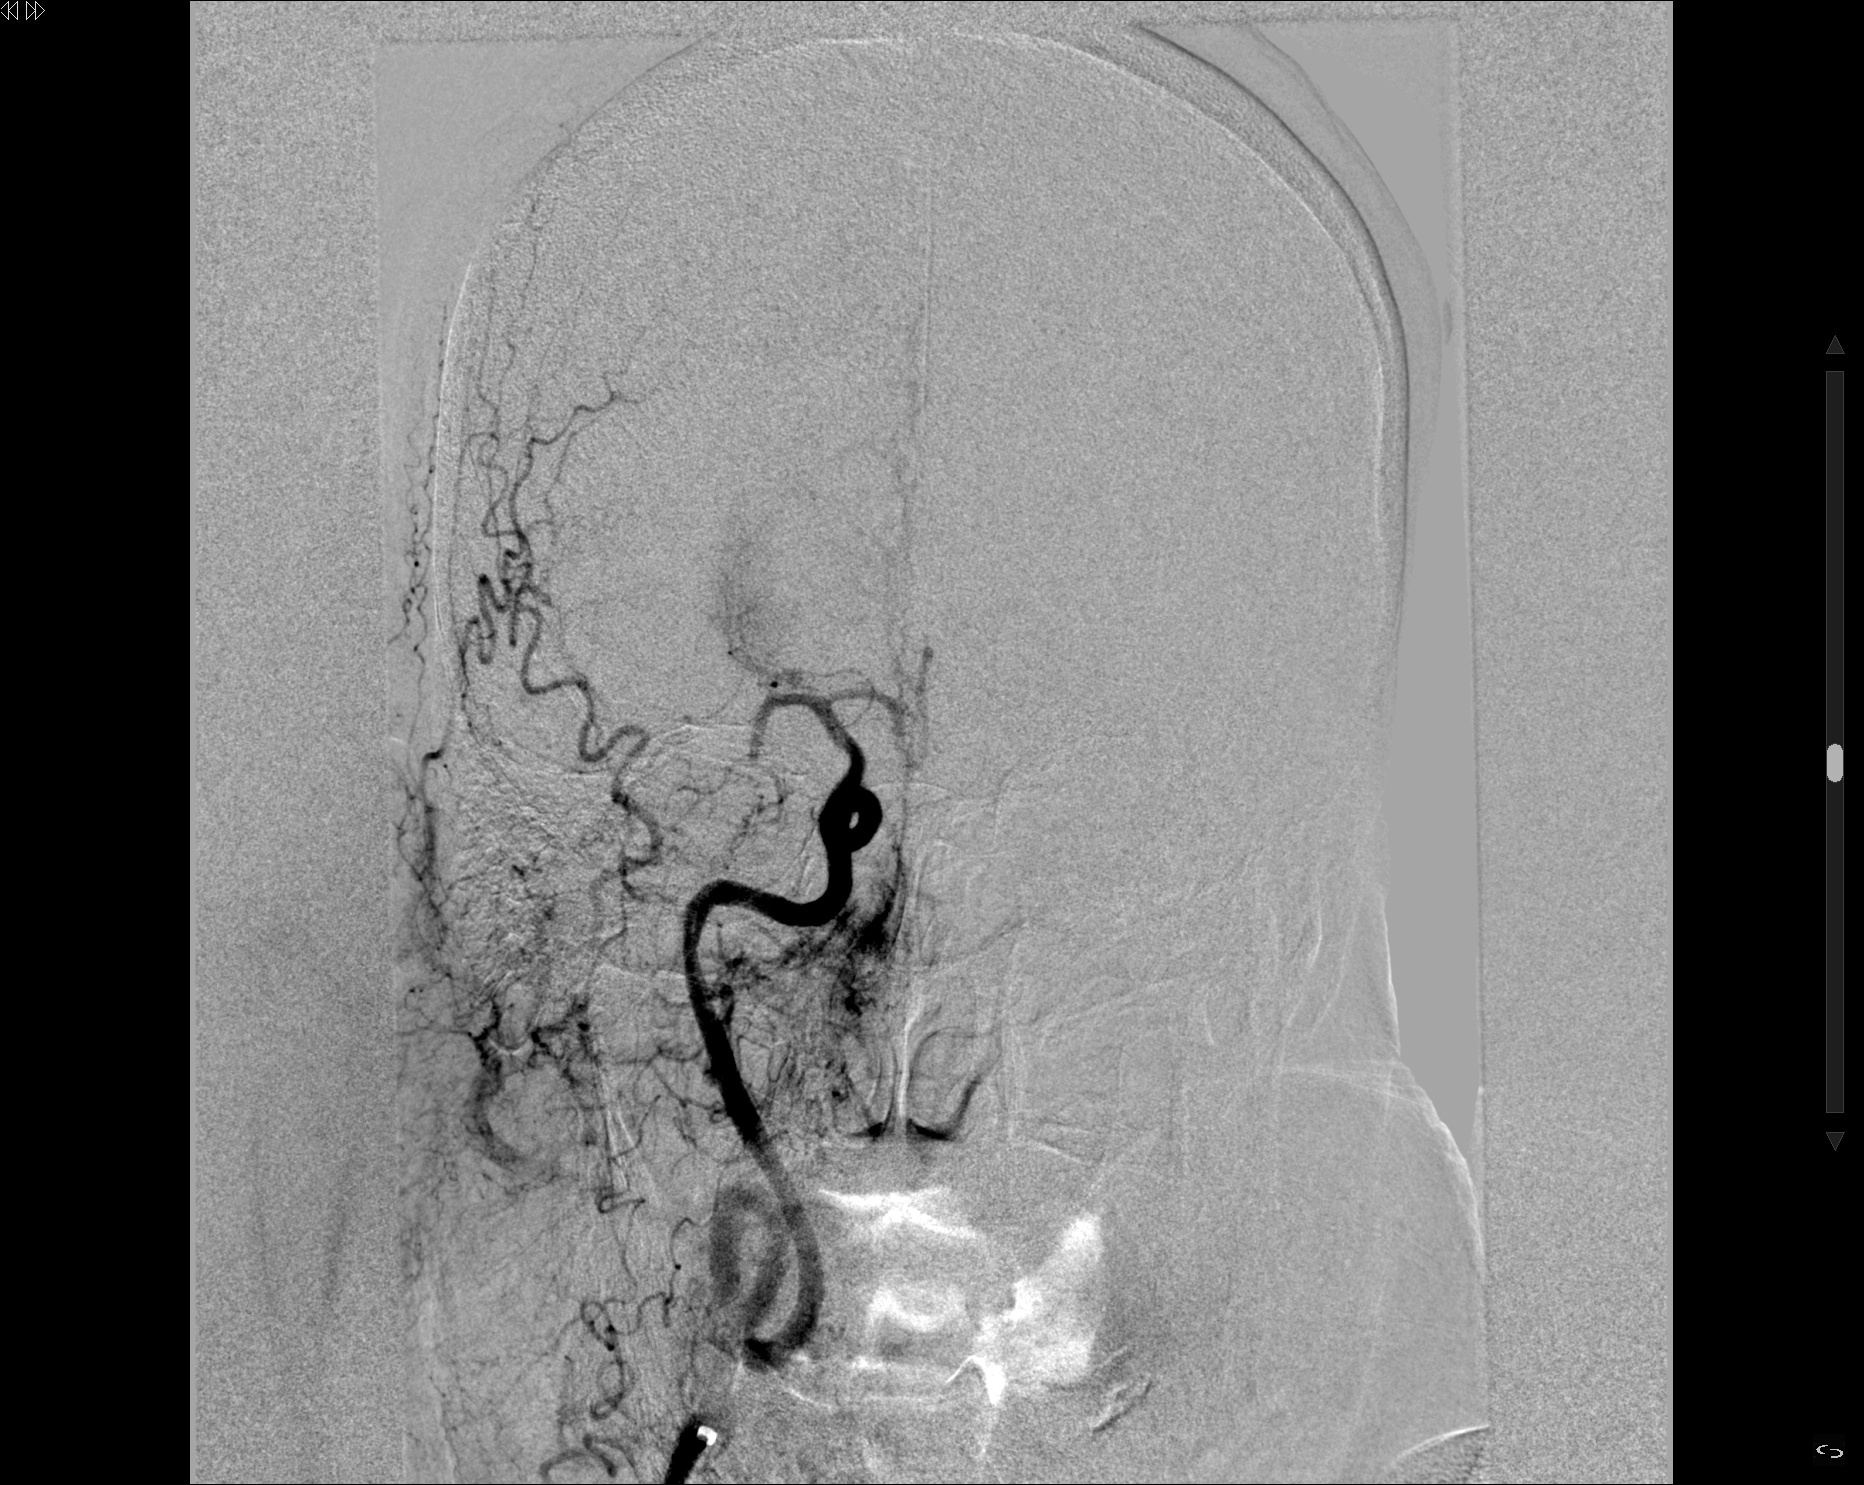

Se realiza punción femoral derecha. Se realiza cateterización selectiva de la arteria carótida común izquierda derecha y la primera serie angiográfica pone de manifiesto una estenosis mayor del 80% secundario a placa irregular ulcerada en el origen de la ACID. Se atraviesa

estenosis y se realiza angioplastia con balón. Se avanza introductor largo hasta ACID y se realiza serie sectiva observando una oclusión a nivel del segmento carotida terminal en T. Se procede al microcateterismo selectivo de arteria ocluida logrando una adecuada posición para realizar trombectomía, realizando 1 pase. En la serie de comprobación final se confirma recanalización TICI 2b, quedando oclusión distal en ACA (A3). Se realiza nueva serie en carótida común observando persistencia de estenosis con una placa ulcerada e

irregular en el origen de ACID. Se coloca un filtro en ACI distal de protección y se decide colocación de 2 Stent en ACI proximal de 9×40 y un segundo Stent 7×40, con resultado posterior satisfactorio, sin estenosis significativa residual